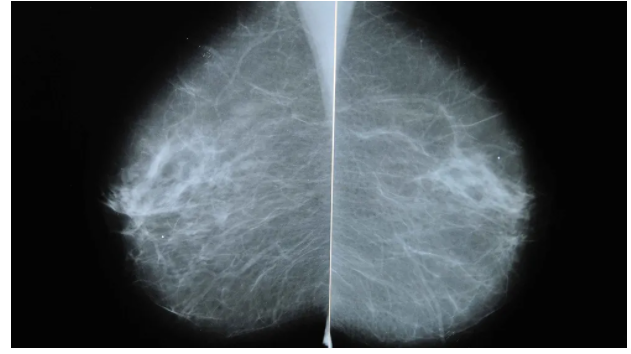

Devon Quasha是一名医护人员,平时就很关注自己的身体健康,所以当她发现乳房周围有肿块时,便立即预约了X光和超声检查。

在做检查的前几天,Devon感觉整个左臂、腋下和锁骨上方的部位都开始出现异常的肿胀。

万幸的是,医生看了报告认为她患癌症的几率不大,并且告诉Devon,之所以出现肿胀的症状是因为她才接种过新冠疫苗。

原来在预约检查前的一周,作为医护人员的Devon注射了第一针Moderna疫苗。

相关数据显示,大约有10%的群众在接种第一剂Moderna疫苗后,腋下或锁骨周围的淋巴结部位会出现肿块,这也是打完疫苗后产生的常见副作用之一。

来自渥太华的乳房影像科主管医师Jean Seely表示,不仅是女性,男性在注射完疫苗后也会经历类似的副作用,通常在打完疫苗后数周内"发作"。

然而这个说法并不能让Devon感到完全放心,她的放射科医生也称,因新冠疫苗造成的肿块是一方面,可乳房周围出现的肿块是另一回事,需尽快进行活检确认。

但由于Devon打了疫苗没多久,医生又不建议她立刻进行活检检查,否则很可能导致被误诊为罹患乳腺癌。